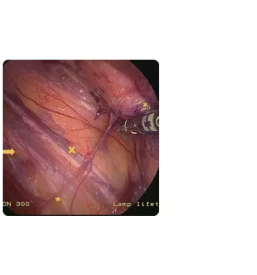

Športnikova kila je izraz za bolečinski sindrom v dimljah, ki je precej kompleksen tako glede diagnostike, kot samega zdravljenja.

Razlogov za bolečino v dimljah je veliko, lahko gre za pravo kilo, ki se vidi kot izboklina iz trebuha ob napenjanju, pogosti vzroki so lahko okvare hrbtenice, pri katerih bolečina pasasto seva v dimlja, možni pa so tudi razni urološki vzroki.